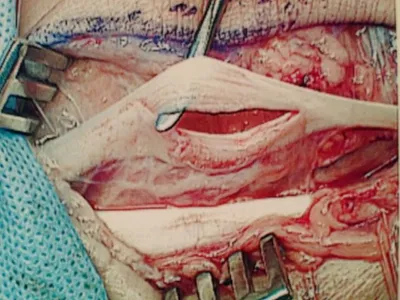

Below, dislocated peroneal tendons are being repaired and reduced to the anatomic location.

The tendons are dislocated to the outside of the fibula instead of behind.

These are intraoperative pics of a woman who traumatically dislocated her peroneal tendons in a fall.

These are pics of the peroneus longus dislocated over the fibula. The instrument on the bottom is pointing towards the tendon. The instrument on the top left is showing where the tendon should be.

This is a pic of us relocating the tendons.